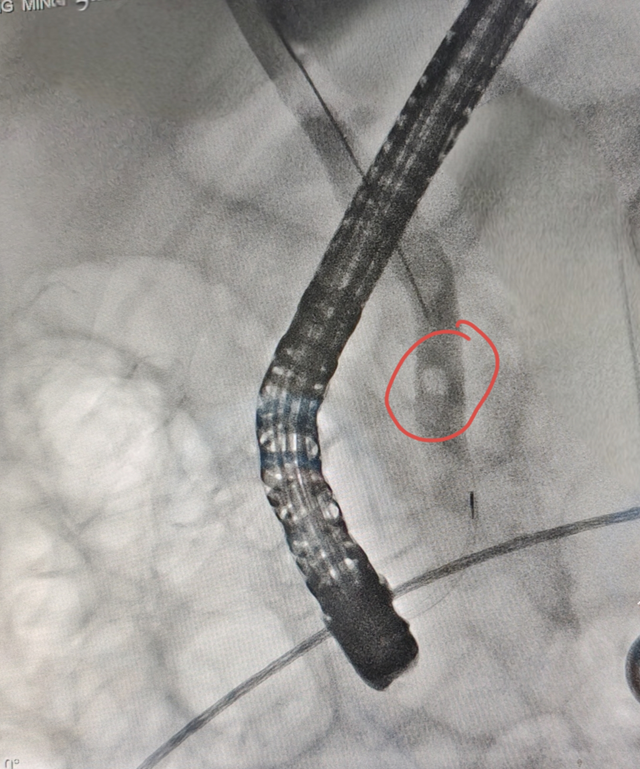

ERC造影见胆总管结石

扩张球囊扩张十二指肠乳头